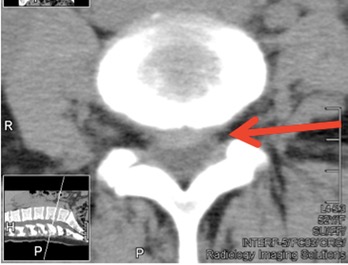

This clinical presentation represents a classic case of disc herniation with severe pain, numbness, and tingling, nights without sleep, inability to walk or sit and immense pain.

The new MRI was NORMAL. The previously reported large L4-5 disc was completely resorbed. (see picture below)

This case represents the growing approach of the conservative treatment of disc disorders with types of equipment like "DRS-9000", "Vax-D," "Flexion Distraction Decompression" and "Vertetrac." We are proud to have the latest equipment of the non-surgical decompression treatment of the discs.